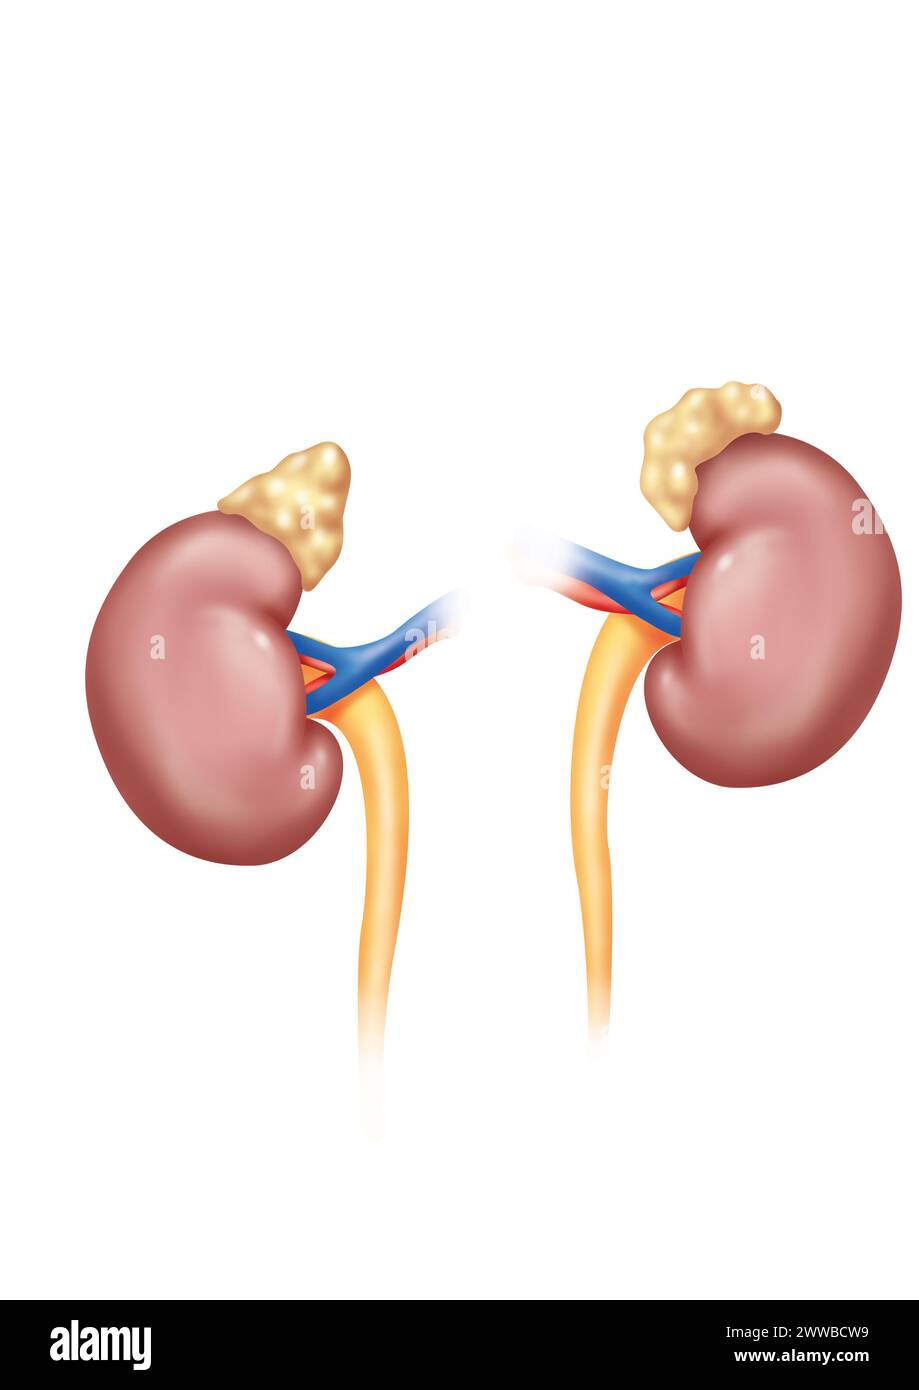

RM2WWBCW9–Reins en vue antérieure avec uretères surrénaliennes et artères et veines rénales. Le rein gauche est placé plus haut que le rein droit.